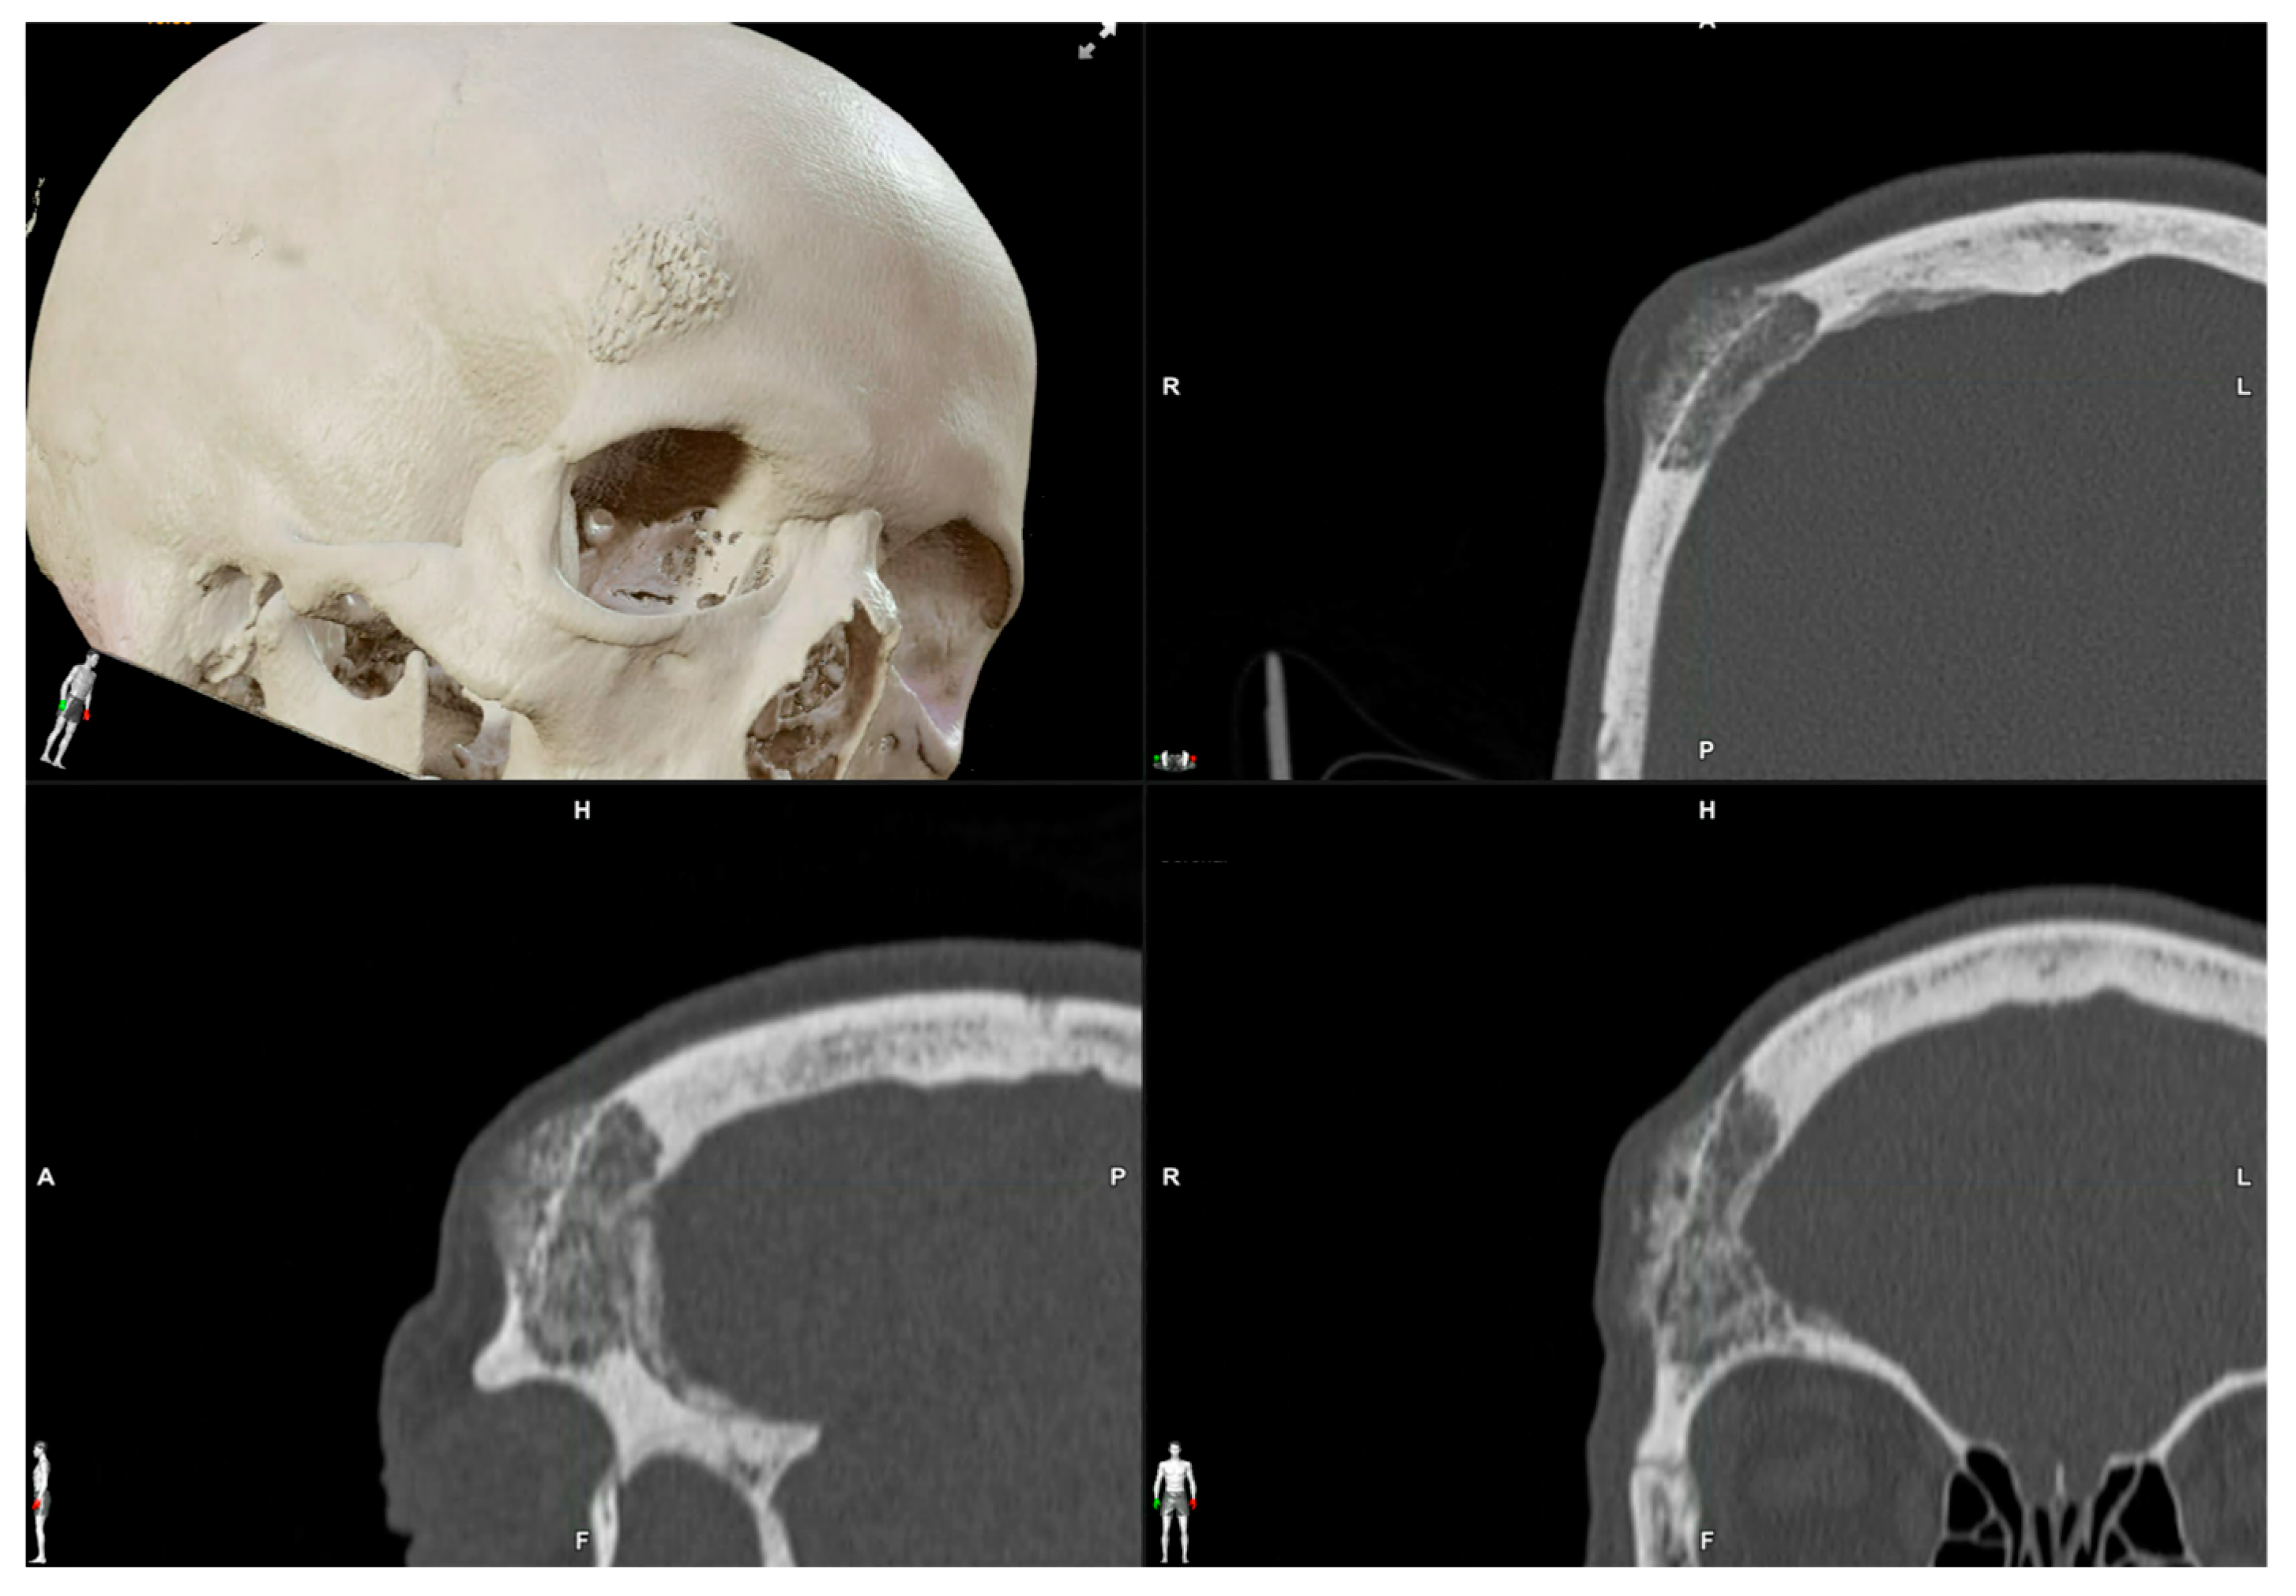

2.3.1. Virtual Surgical Plan

2.3.2. CAD-CAM Design of the PEEK Prosthesis

| 1 | 53/F | L/25 mm | Y | 4 mo | Dystopia | N | CT, MRI | Supraorbital rim, orbital roof | Intraosseous venous malformation | - | Resection + reconstruction | Y | Y | 1st, 2nd, 3rd | Coronal | Y | Piezoelectric device | N | PEEK prosthesis | 7 y/N |

| 2 | 54/F | R/33 mm | Y | 9 y | N | Y | CT, MRI | Frontal bone, orbital roof | Intraosseous venous malformation | - | Resection + reconstruction | Y | Y | 1st, 2nd, 3rd | Coronal | Y | Piezoelectric device | N | PEEK prosthesis | 6 y/N |